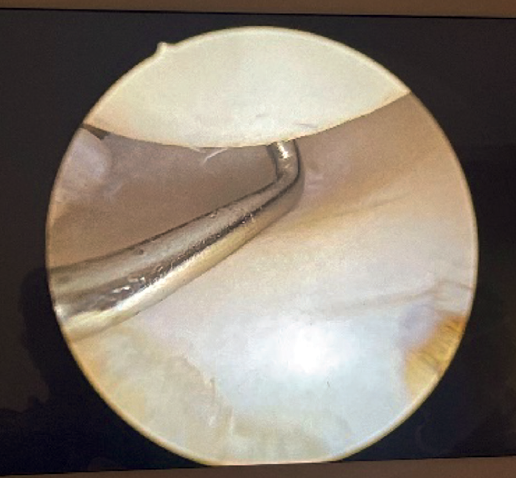

Visioning for lateral complex plication is made through the posterolateral portal. From this portal we access the lateral elbow groove to visualize the posterior part of the radiocapitellar joint. It will also allow us to examine the Osborne-Cotterill lesion component and determine the degree of posterolateral instability by applying varus and supination to the forearm. With this maneuver we can observe how the radial head undergoes subluxation posteriorly and the joint line opens (Figure 2).